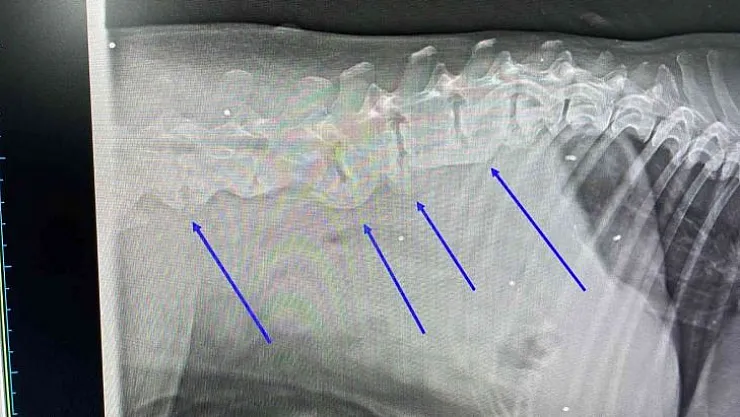

Muğla'nın Bodrum ilçesinde trafik kazası sonucu yaralanan köpeğin çekilen röntgen filminde, daha önce tüfekle vurulduğu ve vücudundaki saçmalarla yaşadığı ortaya çıktı.

Araç çarpması nedeniyle kalçasında kırık olan köpeğin vücudunda onlarca saçmaya rastlandı. Saçmalar, hayvanın daha önce tüfekle vurulduğunu ve vücudunda saçmalarla yaşadığını ortaya çıkardı. Köpeğin ne zaman vurulup ne zamandan beri vücudunda saçmalarla yaşadığı bilinmiyor. Hayvanın tedavisinin özel bir veteriner kliniğinde sürdüğü öğrenildi.